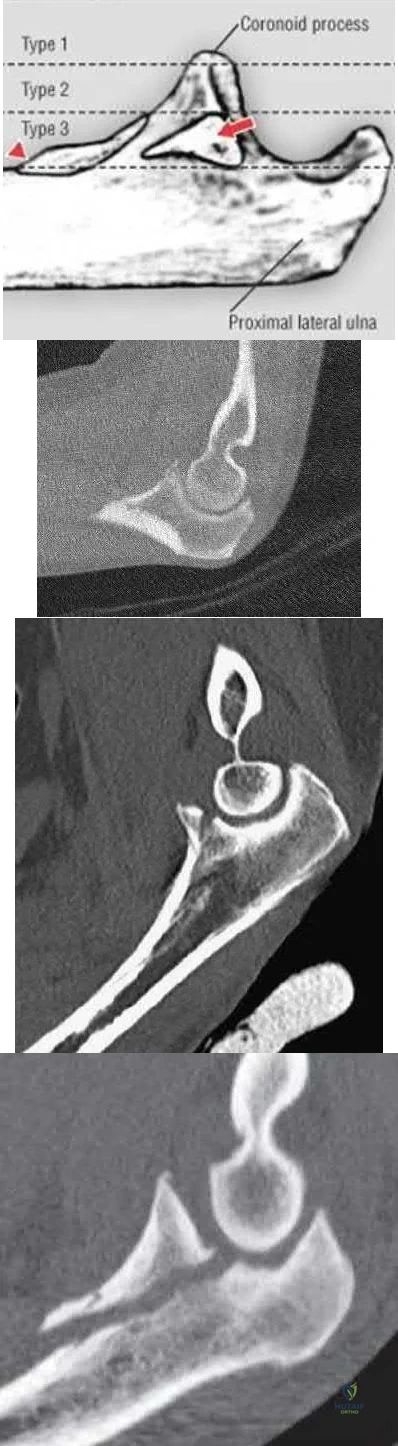

Terrible triad injuries of the elbow are characterized by: 1. Radial head fracture, 2. Coronoid fracture, and 3. Elbow dislocation. Whether to surgically address the coronoid fracture depends on the size of the fragment (Reagan-Morrey types I-III; Illustration A) as well as elbow stability. Reagan and Morrey suggested that small fractures of the coronoid tip (type I) involving less than 10% of the coronoid may represent anterior capsule avulsions; however, recent cadaveric studies demonstrate that the capsule inserts more distally on the tip and that small fractures often do not contain capsule insertion. Gross elbow instability in the presence of a type I fracture is most likely due to an independent MCL injury and NOT the coronoid avulsion. Surgical repair of type I fractures has not been shown to affect stability and may detrimentally affect elbow range of motion.

Illustration A demonstrates the Regan-Morrey classification of coronoid fractures. Type I fractures involve < 10% of the coronoid tip and do not result in significant elbow instability. Type II fractures involve < 50% of the coronoid and may result in elbow instability secondary to loss of the anterior bony buttress that resists posterior displacement of the ulna, as well as loss of the anterior capsule insertion. These fractures are often repaired, particularly when associated with elbow instability. Type III fractures involve > 50% of the coronoid and often contain the insertion of the anterior band of the MCL (red arrow). The insertion of the brachialis (red triangle) may also be involved resulting in proximal displacement of the fracture fragment. Surgical repair of type III fractures is necessary to reconstitute the MCL and restore elbow stability. Illustration B is a CT scan of a type I coronoid fracture. Illustration C is a CT scan of a type II coronoid fracture. Illustration D is a CT scan of a type III coronoid fracture.